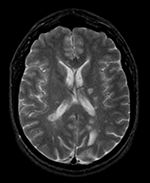

Slicer Registration Library Case 04: Intra-subject Brain MR of Multiple Sclerosis: Multi-contrast series for lesion change assessment

This scenario occurs in many forms whenever we wish to assess change in a series of multi-contrast MRI. The follow-up scan(s) are to be aligned with the baseline, but also the different series within each exam need to be co-registered, since the subject may have moved between acquisitions. Hence we have a set of nested registrations. This particular exam features a dual echo scan (PD/T2), where the two structural scans are aligned by default. The post-contrast T1-GdDTPA scan however is not necessarily aligned with the dual echo. Also the post-contrast scan is taken with a clipped field of view (FOV) and a lower axial resolution, with 4mm slices and a 1mm gap (which we treat here as a de facto 5mm slice).

Unregistered baseline data: PD vs. T1Gd Unregistered followup data: PD exam 2 vs. exam 1

Registered baseline data Registered followup data

Lesion change visualization in 3D Lesion change via subtraction imaging of co-registered PD